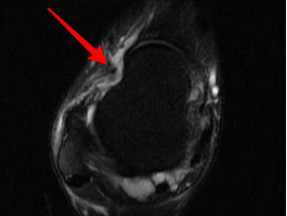

韌帶斷裂

幾經(jīng)輾轉(zhuǎn),李先生來到廣安醫(yī)院就診,骨科中心主任羅軍副主任中醫(yī)師為他進行了詳細專業(yè)的查體,結(jié)合影像檢查,診斷為右踝關(guān)節(jié)不穩(wěn)(距腓前及跟腓韌帶斷裂)、右踝關(guān)節(jié)創(chuàng)傷性關(guān)節(jié)炎。羅軍主任帶領(lǐng)大家詳細分析病情之后,決定為他施行踝關(guān)節(jié)鏡下病變組織清理和距腓前韌帶、跟腓韌帶重建術(shù)。